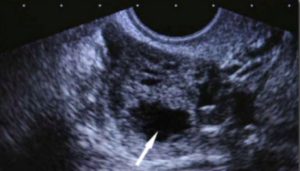

- УЗИ. В полости кисты отсутствуют кровеносные сосуды. Это является отличительной характеристикой лютеинового новообразования.

Во время гинекологического осмотра врач может найти уплотнения, образовавшиеся в области придатков. Определить наличие кист во время беременности можно на УЗИ с использованием вагинального датчика.

- УЗИ брюшной полости показывает объемные эхогенные новообразования и дает оценку их размерам. Во время беременности на УЗИ достаточно сложно определить желтое тело, из-за его небольшой величины;

- отличить кистозное желтое тело от опухолей яичников поможет цветовая допплерография;

Отличительной особенностью такого новообразования является полное отсутствие в его полости кровеносных сосудов. Определить это может квалифицированный врач-сонолог с помощью хорошего аппарата УЗИ.